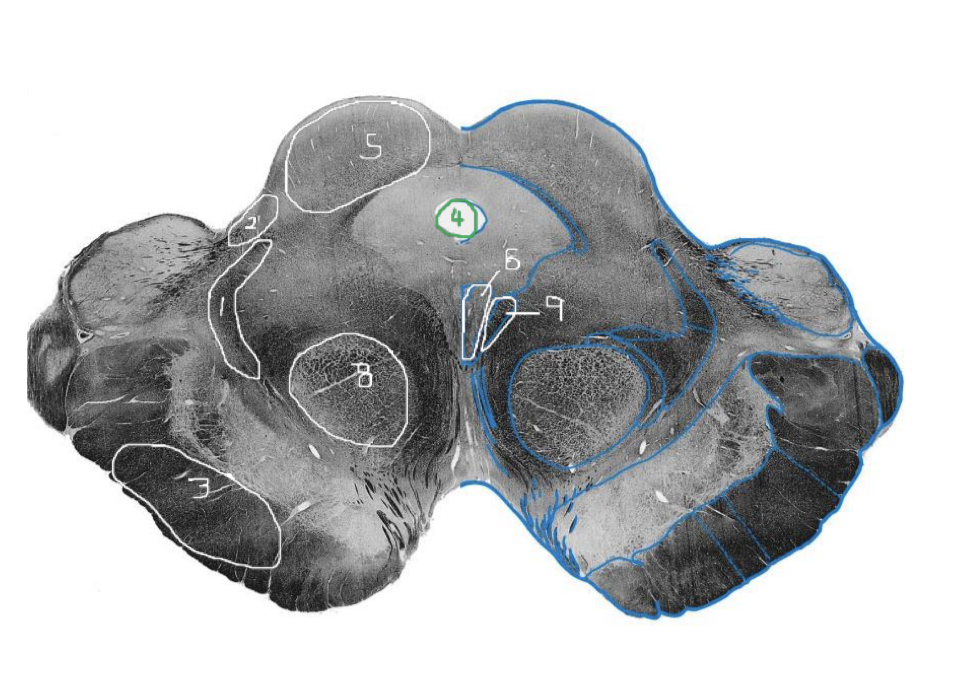

1

Medial Lemniscus - Caudal Pons

2

Spinothalamic Tract - Caudal Pons

3

CST - Caudal Pons

4

4th Ventricle - Caudal Pons

5

Inferior Cerebellar Peduncle - Caudal Pons

6

Middle Cerebellar Peduncle - Caudal Pons

7

Superior Cerebellar Peduncle - Caudal Pons

8

Dentate Nuclei (Cerebellum) - Caudal Pons

9

Inferior Olivary Nucleus - Caudal Pons

10

Medial Longitudinal Fasciculus (MLF) - Caudal Pons